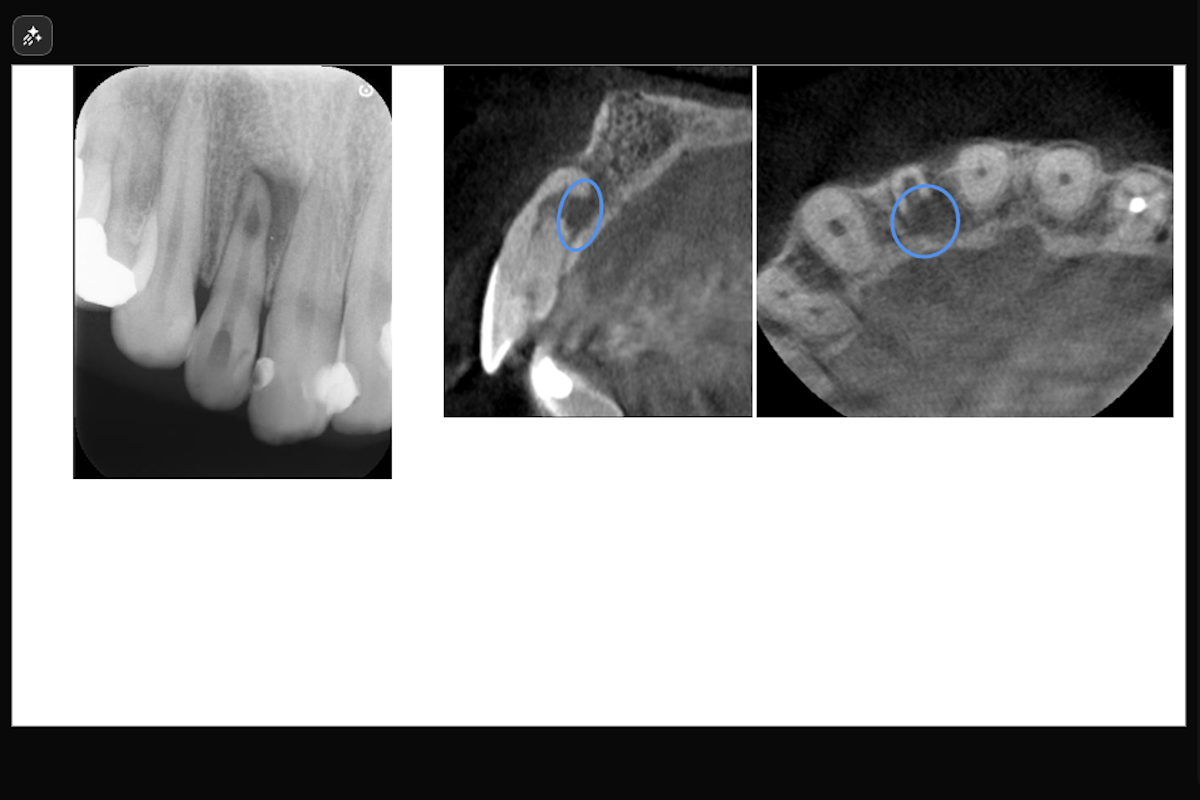

【根尖内部吸収および穿孔を伴う上顎右測側切歯の症例】「近医より紹介、咬むと痛い。」

「近医より紹介、咬むと痛い。」ということで来院された患者様の症例です。

- 根尖内部吸収および穿孔を伴う上顎右測側切歯の症例

- 主訴:近医より紹介、咬むと痛い。

- 治療内容: 上顎右側側切歯 根管治療(レーザーを用いた根管洗浄、MTAを用いた根管充填)